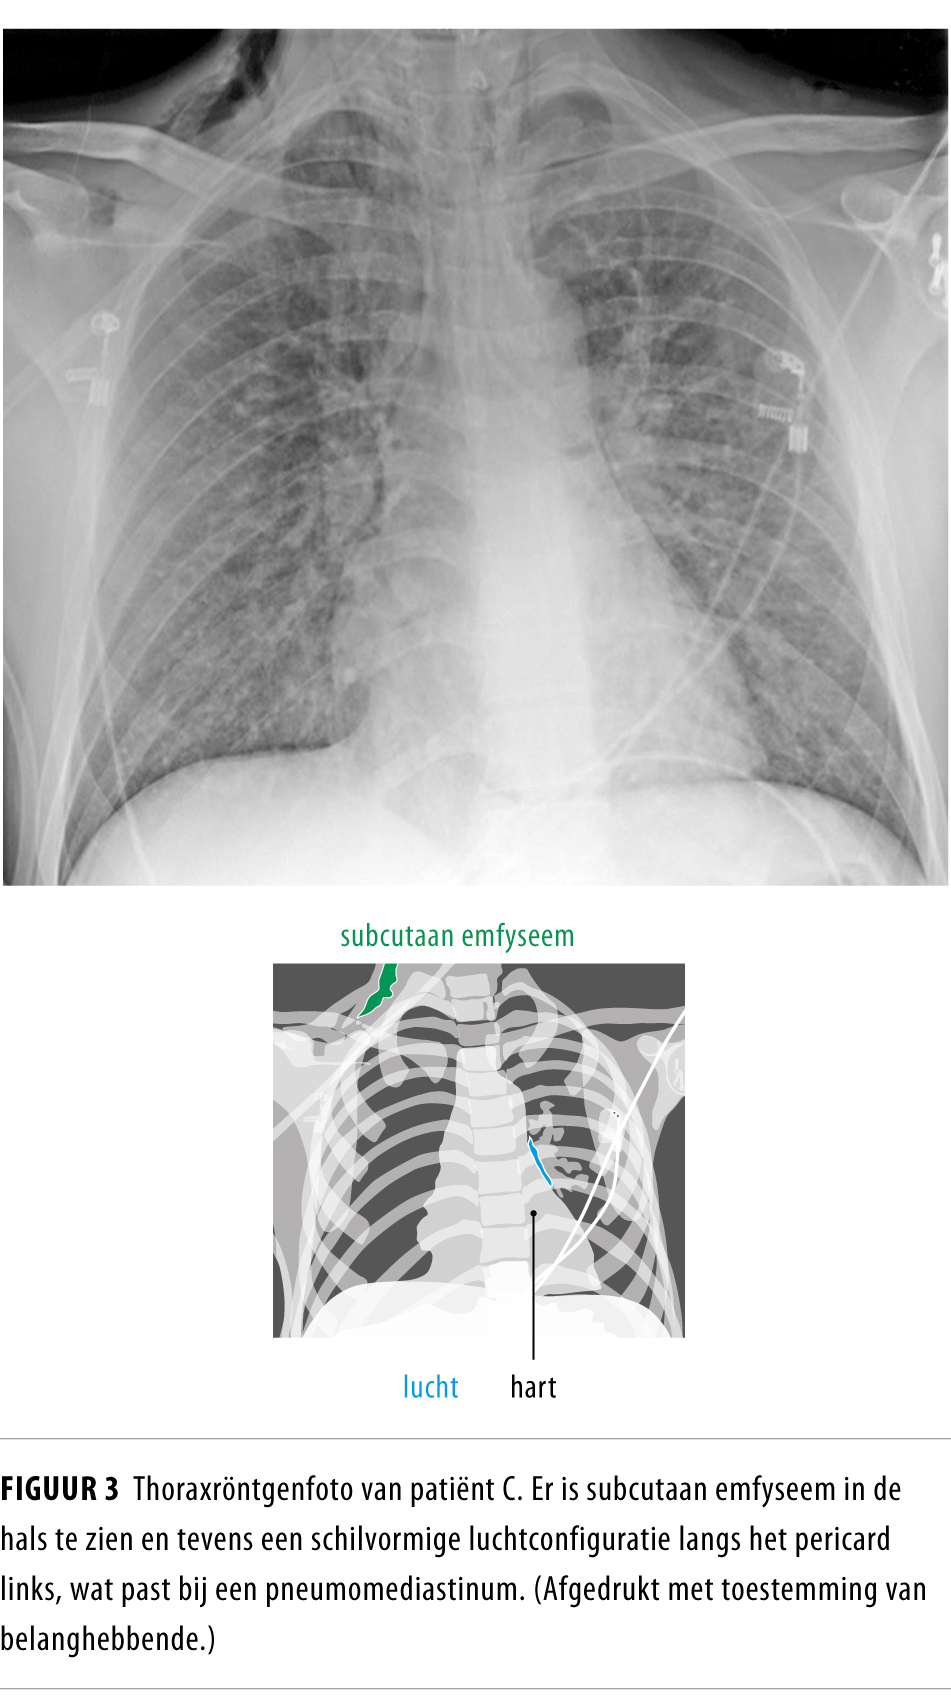

From www.ntvg.nl

Pneumomediastinum ingrijpen is niet altijd vereist Nederlands Wat Is Tachypneu It can be a sign of various. tachypnea is rapid, shallow breathing that makes you feel like you’re not getting enough air. It can have various causes, such as infections, asthma, heat,. Learn how to recognize the signs of tachypnea, what tests your doctor may perform, and how to treat the underlying cause. Tachypnea refers to rapid breathing, typically. Wat Is Tachypneu.